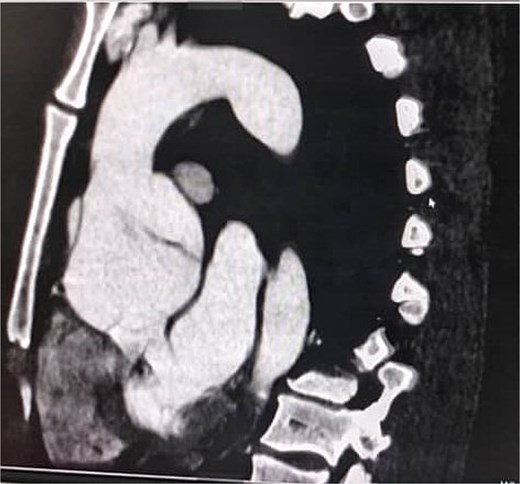

A 33-year-old man with a history of Marfan syndrome and former tobacco use presented with three months of recurrent chest pain. Transesophageal echocardiography (TEE) showed an aneurysmal ascending aorta with an anteroposterior diameter of 67 mm, a dissection extending to the descending aorta, and grade III aortic regurgitation. Thoracic CT angiography (angioCT) confirmed a dissection of the ascending aorta and a fusiform dilation of 67 mm limited to this segment (Fig. 1). A median sternotomy was performed, followed by aortic and atriocaval cannulation. Intraoperatively, the intimal flap was identified 2 cm above the sinotubular junction on the anterolateral side of the ascending aorta, extending to the descending aorta. The patient underwent a modified valve-sparing aortic root replacement (Tyrone David procedure) following the El Arid–Modine technique (Fig. 2a–e). Cardiopulmonary bypass (CPB) and aortic cross-clamp times were 166 and 143 minutes, respectively. Postoperative TEE showed minimal aortic regurgitation. Recovery was uneventful, and no complications were observed over six months of follow-up.

Coronal CT angiography showing a chronic dissecting aneurysm of the ascending aorta.